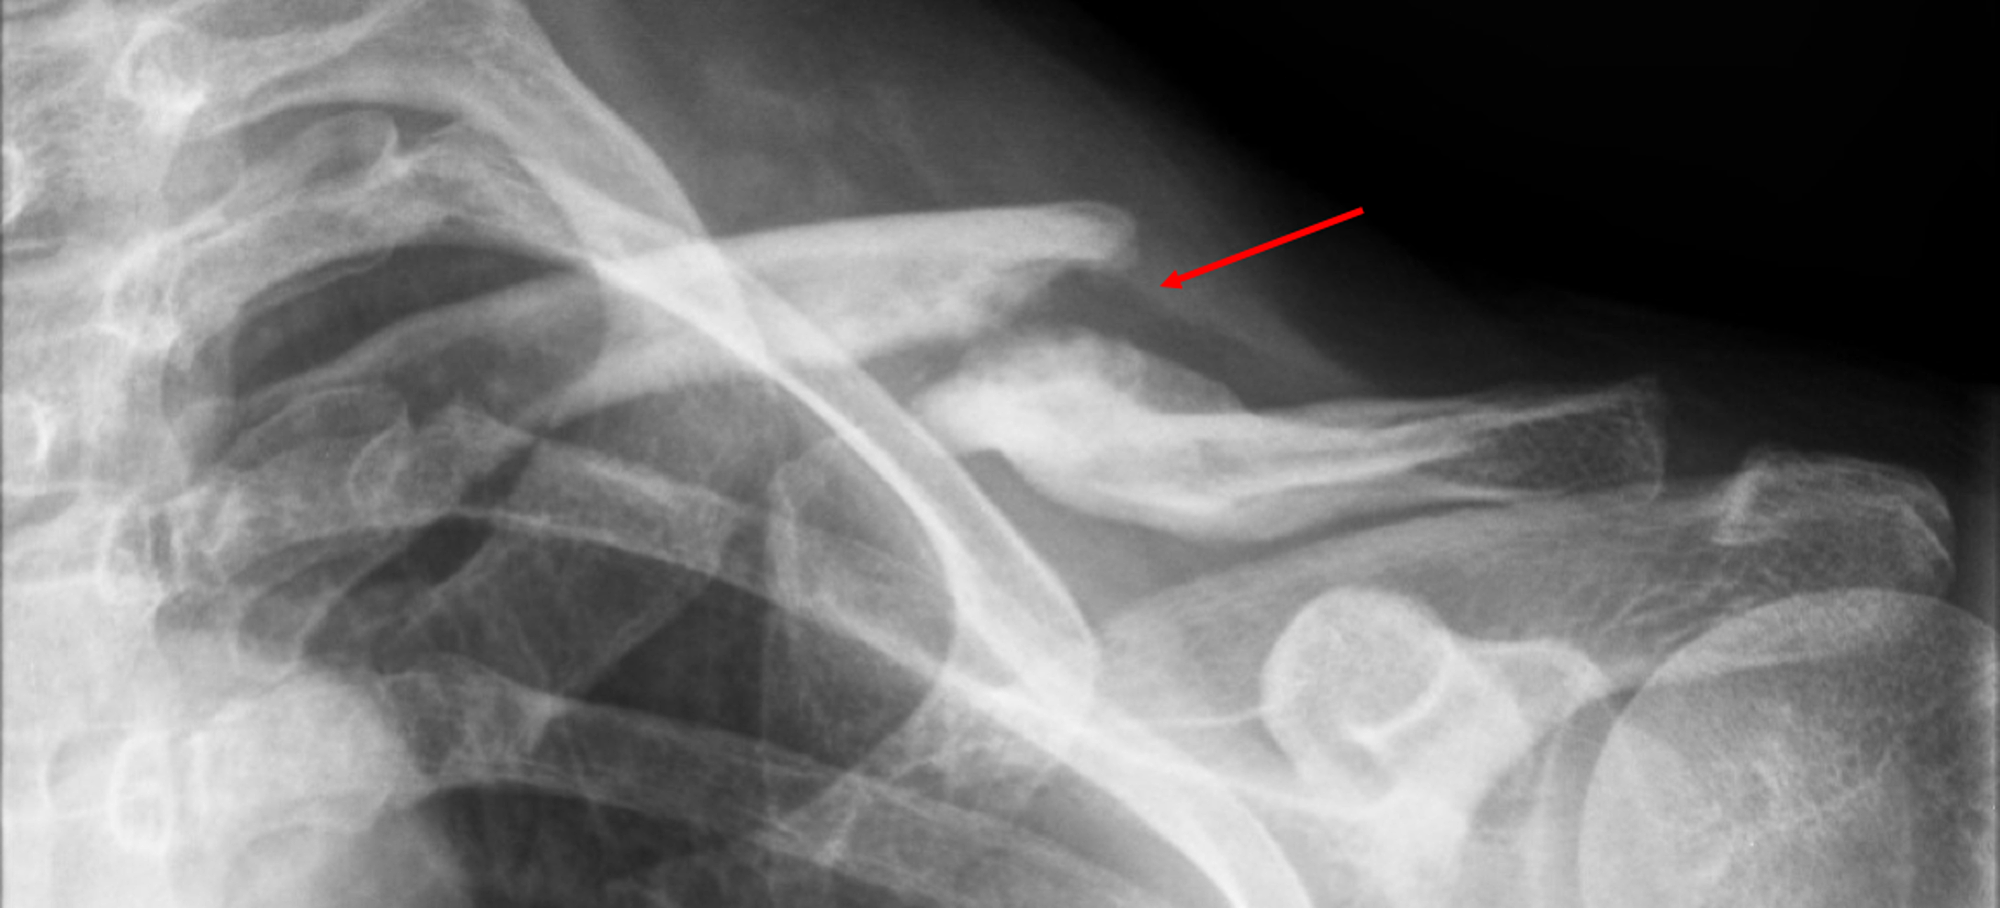

(a) Left closed comminuted midshaft clavicle fracture; (b) fracture end Midshaft Clavicle Fracture Jaaos midshaft clavicle fractures. Paul hoogervorst, peter van schie, and michel pj van den. operative treatment of displaced midshaft clavicle fractures in adult patients is associated with higher union. fractures of the clavicle are common injuries that occur across all age groups but are most frequently seen in the. midshaft clavicle fractures are common traumatic injuries caused. Midshaft Clavicle Fracture Jaaos.